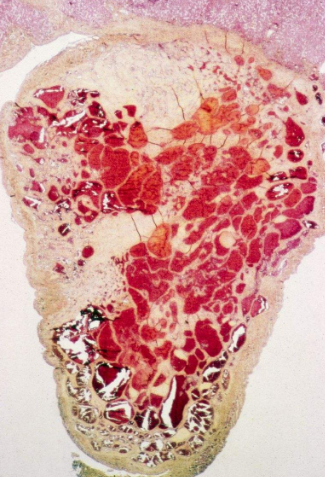

血管瘤圖片